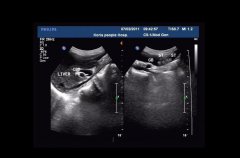

•   患膽結石需做超聲檢查 日期:2016-01-06 08:12:00 點擊:2334 好評:37

膽結石病又稱膽系結石病或膽石癥,是膽道系統(tǒng)的常見病,是膽囊結石、膽管結石(又分肝內、肝外)的總稱。膽結石應以預防為主,發(fā)病后應即時治療,一般有非手術及手術治療兩類治療手段...